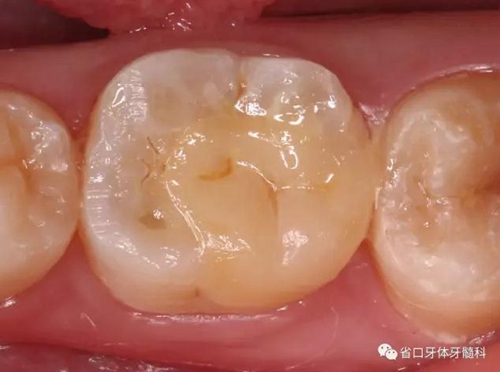

圖2 根管治療術(shù)后即刻X線片